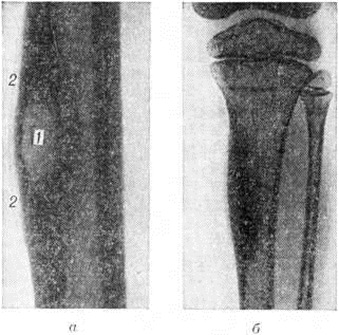

В диагностике Остит, помимо изучения клинические, симптомов, важное значение имеет рентгенологические исследование соответствующего участка скелета как минимум в двух стандартных (прямой и боковой) проекциях. Основным рентгенологическое признаком Остит является деструкция костного вещества, проявляющаяся на рентгенограммах просветлением его тени. Разрежение костного вещества при Остит носит очаговый характер. Деструктивный очаг медленно увеличивается в размерах (от нескольких миллиметров до нескольких сантиметров); по периферии очага развивается реактивный остеосклероз (смотри полный свод знаний). Для остеомиелита и туберкулёзного Остит характерно образование в деструктивной полости костного секвестра. При томографии (смотри полный свод знаний) иногда обнаруживают невидимые на обычных рентгенограммах мелкие деструктивные очаги или получают более наглядную картину деструкции. Остит вызывает в большинстве случаев продуктивную реакцию надкостницы, а иногда и эндоста. В этом случае воспалительный процесс характеризуется наличием деструктивного дефекта в корковом веществе периостальных наложений, вызывающих утолщение кости (рисунок, а). При оссифицирующем Остит кость на рентгенограмме выглядит уплотнённой и утолщённой (рисунок, б). Такая картина наблюдается при остеомиелите Гарре, сифилисе.